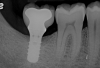

Pretreatment radiograph of a peri-implantitis

lesion on a 51-year-old male patient with a noncontributory medical history. The implant had been placed 3 years prior and presented with 8 mm pocketing with purulence.

Figure 1